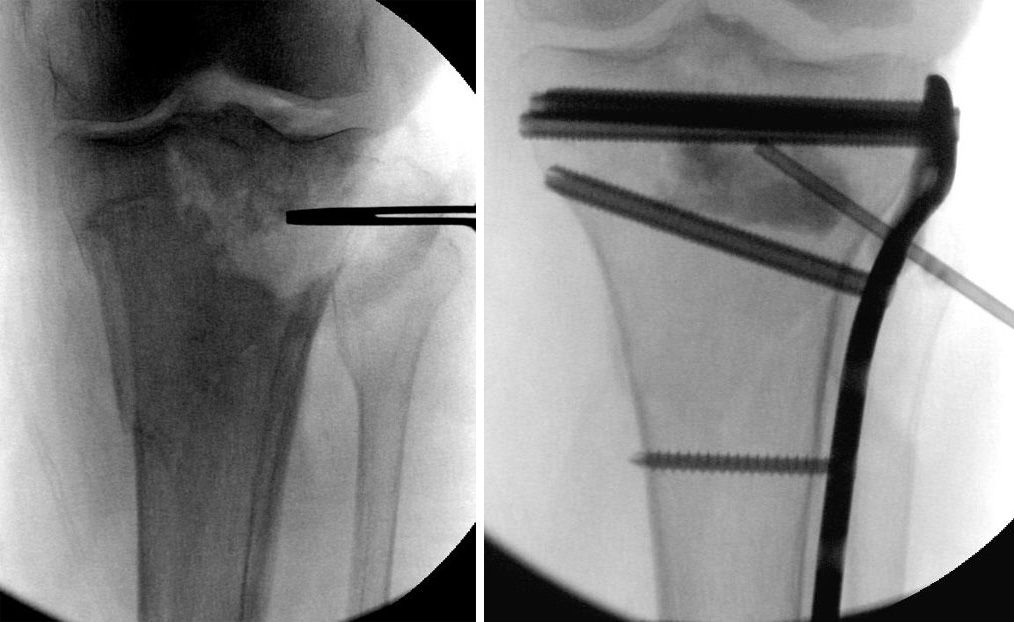

External fixation of proximal tibia fracture

Soon after an accident, the injured skin and soft tissues may be further harmed by surgery. In this event, a temporary external fixator may be applied to support the limb until the soft tissues recover and surgery can safely be performed.

External fixation. If the soft tissues (skin and muscle) around your fracture are badly damaged, or if it will take time before you can tolerate a longer surgery because of health reasons, your doctor may apply a temporary external fixator. In this type of operation, the surgeon places metal pins or screws into the middle of the femur and tibia. The pins and screws are attached to a bar outside the skin. This device holds the bones in the proper position until you are ready for surgery.